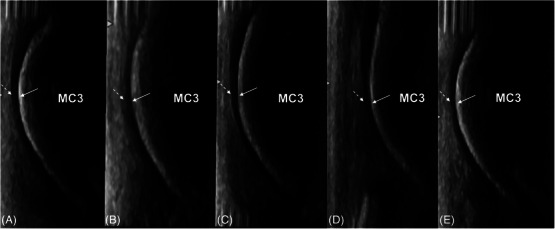

Articular cartilage can be directly imaged using ultrasonography. The fetlock is a common site of osteochondrosis, with the sagittal ridge of the third metacarpal bone most commonly affected. In osteochondrosis, cartilage thickening may be an initial finding. This postmortem study investigated the ability of ultrasonography to accurately measure the dorsodistal articular cartilage of the third metacarpal bone in young horses, compared to computed tomographic arthrography (CTA) and histological measurements. A total of 33 metacarpophalangeal joints from 18 horses between the ages of 12 days and 10 months old were imaged ultrasonographically and with CTA and sectioned and measured using histology. Imaging measurements were made by two observers. Despite overall weak agreement between ultrasonography and histology, the best agreement was at the distal aspect of the sagittal ridge of the third metacarpal bone. Interobserver agreement at this site was also moderate. CTA showed poor agreement overall with histology. Cartilage thickness decreased with age on ultrasonography, CTA, and histology. In conclusion, ultrasonography is a more accurate imaging modality than CTA in the assessment of cartilage in young horses.